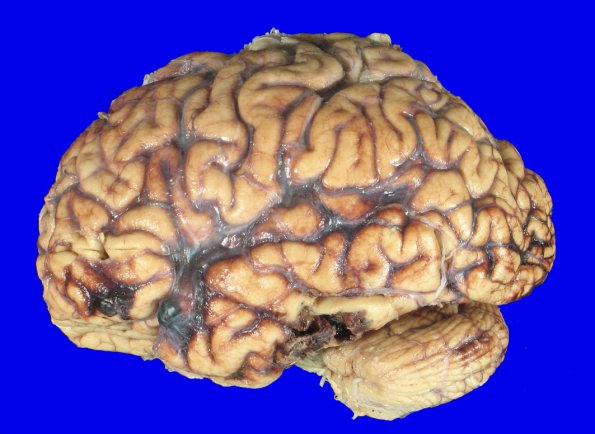

3A4 Contusion & SDH (fall on stairs, Case 3) 2

3A4,5 The left inferior frontal gyrus shows subarachnoid hemorrhage and an underlying cortical contusion.